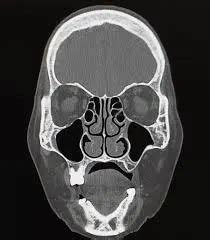

If you have been suffering from persistent sinus pressure, chronic congestion, or mysterious facial pain, your healthcare provider may recommend a Nasal CT scan to get a clearer picture of what is happening inside your nasal passages. This specialized imaging procedure is a cornerstone of modern otolaryngology, providing doctors with high-resolution, three-dimensional views of the complex structures within your nose and paranasal sinuses. Unlike a standard X-ray, which offers a two-dimensional look, a computed tomography (CT) scan provides detailed cross-sectional images, allowing specialists to pinpoint inflammation, structural abnormalities, or obstructions with remarkable accuracy.

A Nasal CT scan, often referred to as a sinus CT scan, is a non-invasive diagnostic tool that uses X-ray technology paired with advanced computer processing to create detailed images of your sinus cavities and nasal anatomy. When you undergo this scan, you will lie on a table that slides into a doughnut-shaped machine. The scanner rotates around your head, capturing multiple images from different angles to construct a comprehensive view of the area.

The primary purpose of this imaging is to assist ear, nose, and throat (ENT) specialists in diagnosing conditions that cannot be easily visualized during a routine physical examination. Because the sinuses are deep within the skull, traditional physical inspections only show a small portion of the nasal cavity. A CT scan, however, reveals the entire network of sinuses, highlighting potential issues that may require medical or surgical intervention.

Once the images are captured, a radiologist will review them and generate a report. They look for specific markers of health, such as clear, air-filled sinus cavities, versus signs of pathology, such as fluid accumulation, mucosal thickening, or bone erosion. Your ENT specialist will then combine these results with your clinical symptoms to make a definitive diagnosis.

It is important to remember that a Nasal CT scan report is only one piece of the puzzle. An abnormal result does not always indicate a serious condition; for instance, some mucosal thickening might be the result of a mild, lingering seasonal allergy. Your doctor will interpret the findings within the context of your overall health history.